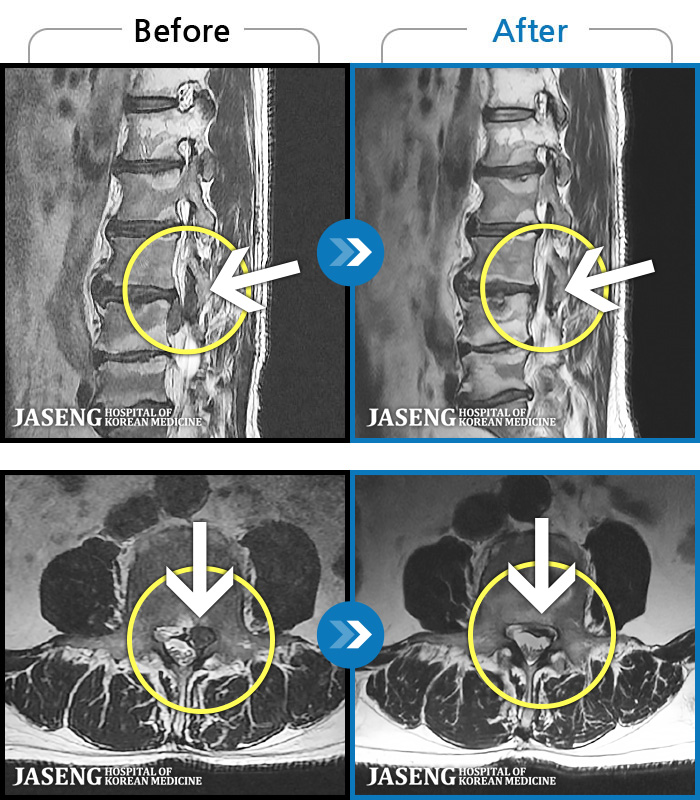

MRI ũ ʸ Ȯϼ.